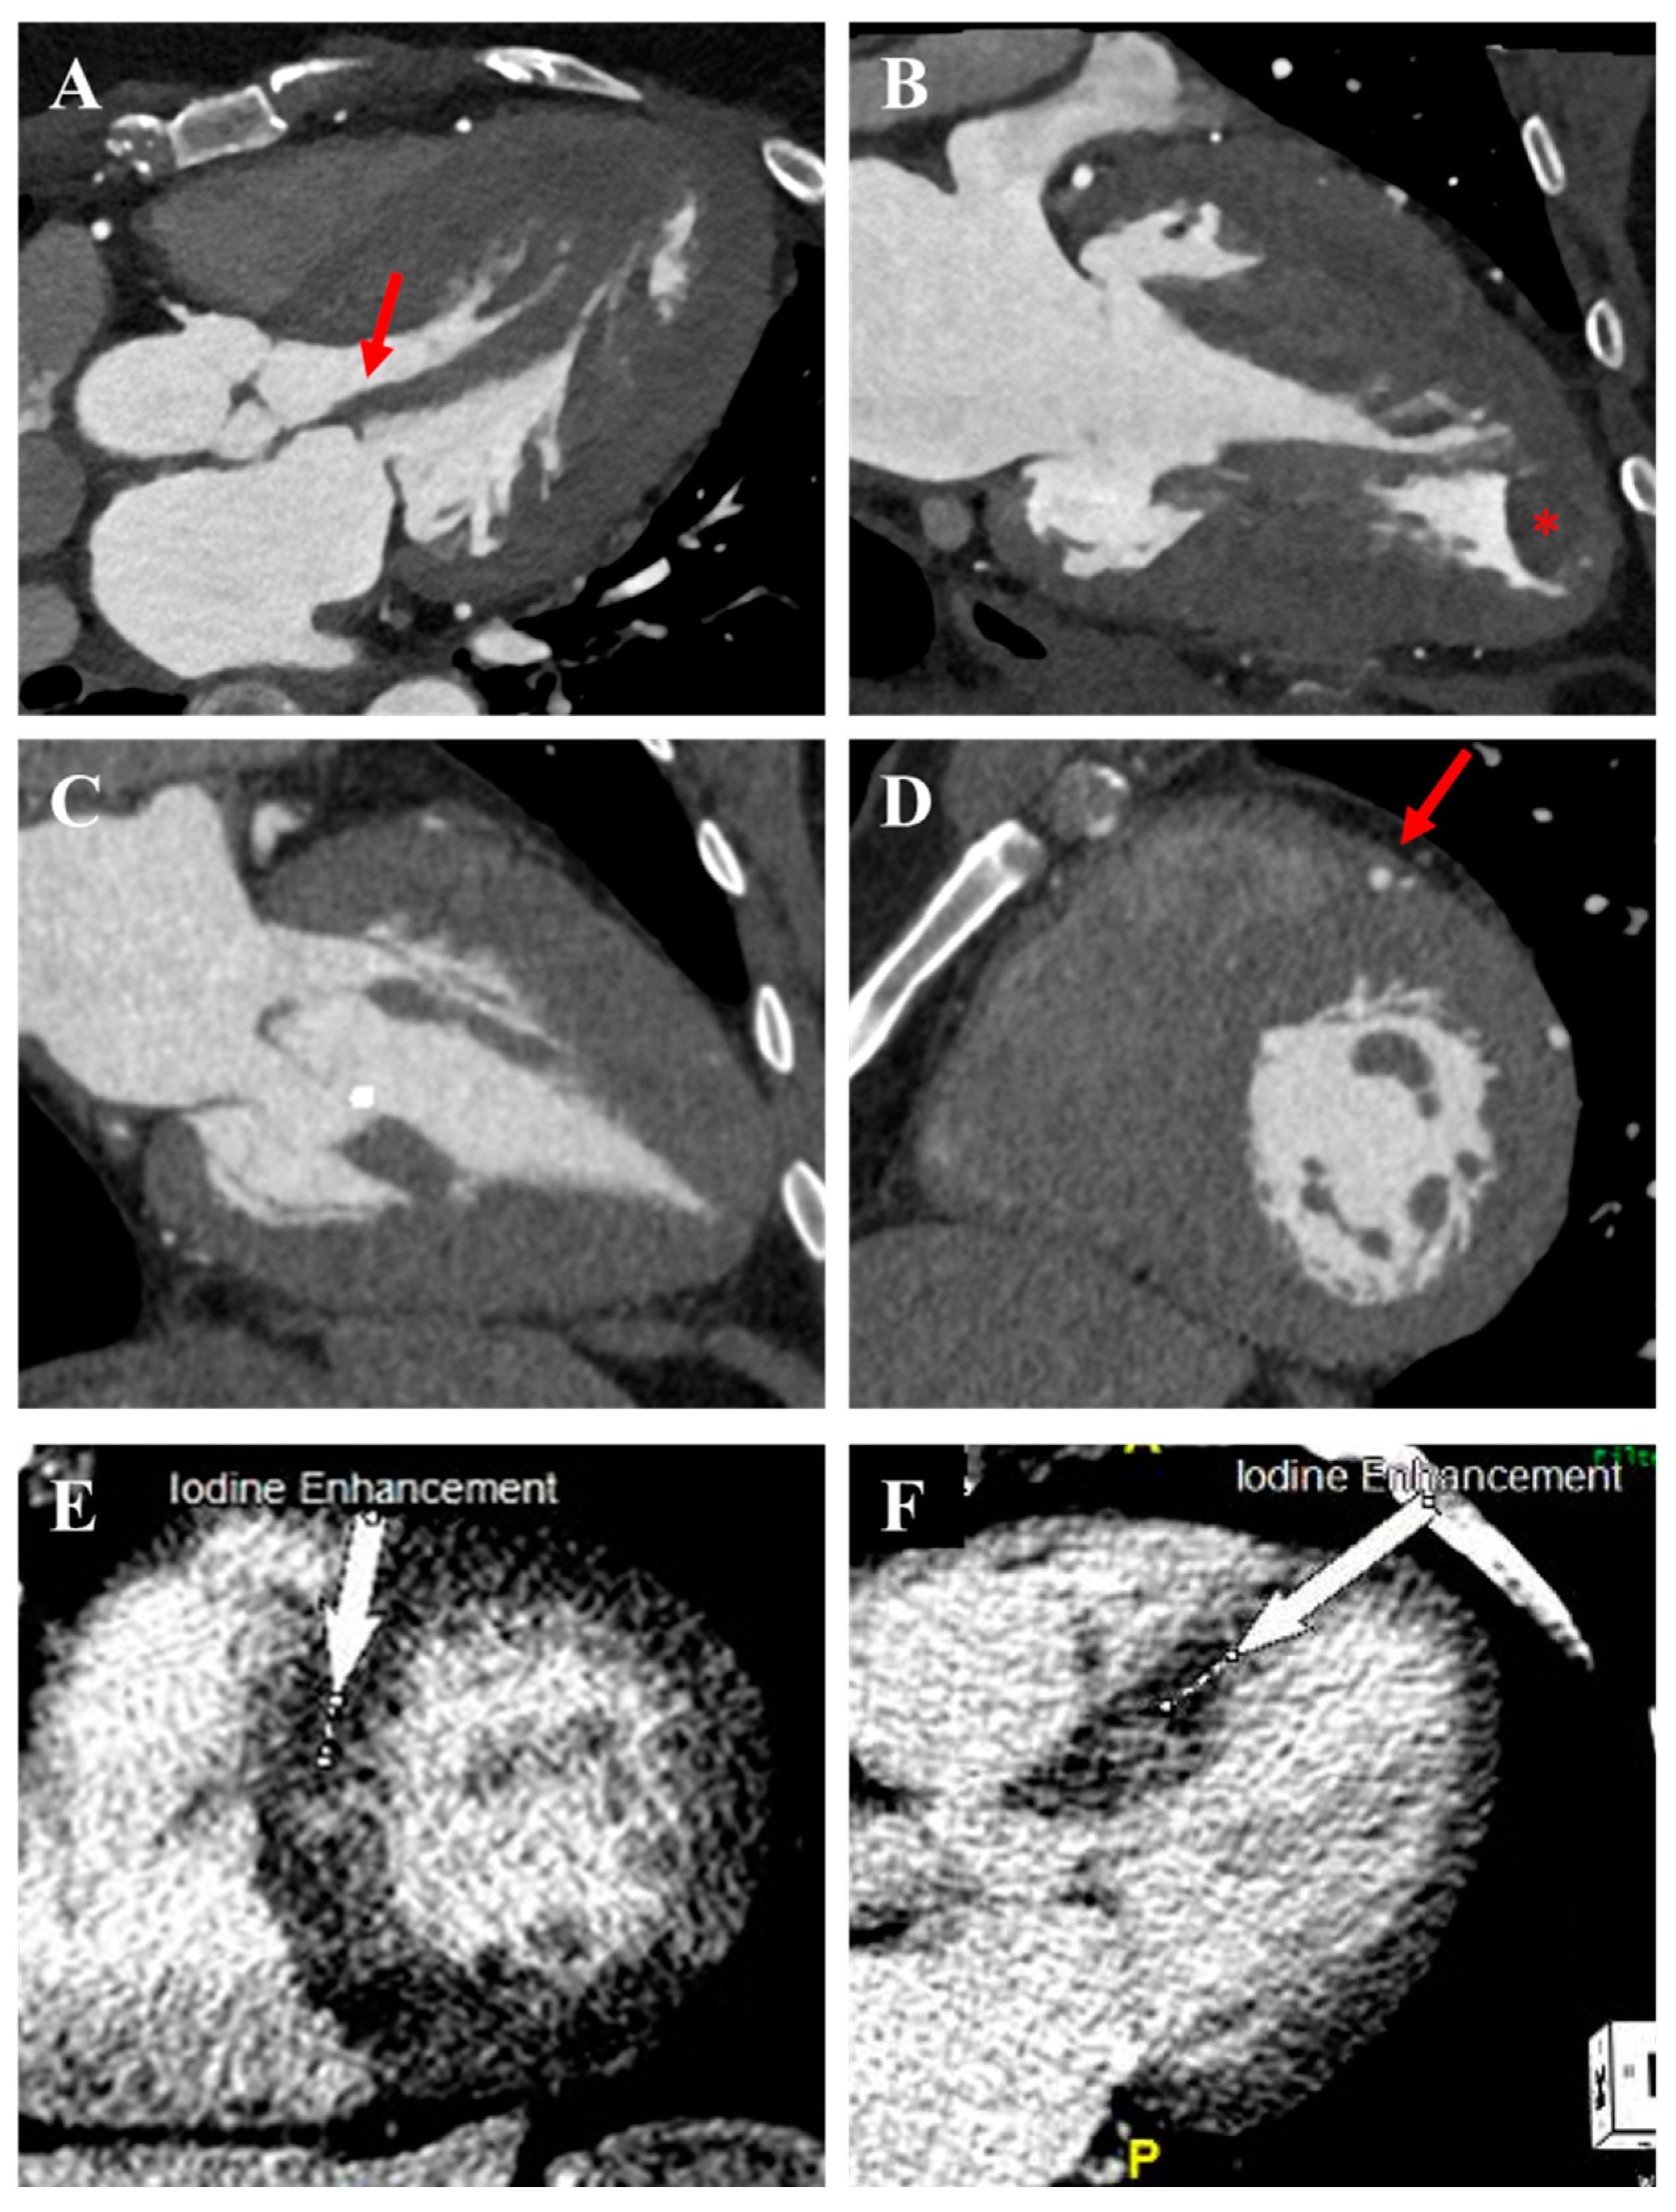

2.4. Apical Aneurysm

3.4. Cardiac Computed Tomography

3.5. Nuclear Myocardial Perfusion Imaging